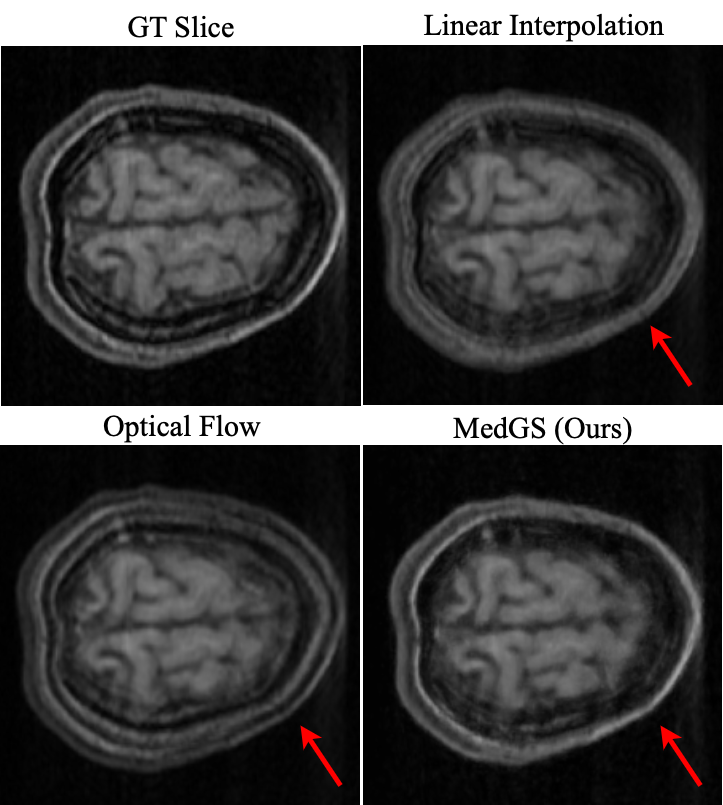

Refer to caption

Figure 6: Qualitative results of frame interpolation on a brain MRI volume. Our method (MedGS) produces a sharper reconstruction.

Interpolation   Interpolation performance is assessed using a leave-frame-out strategy on MRI volumes. Each dataset is sub-sampled in two ways: (i) every 2nd frame, and (ii) every 3rd frame for training, while the held-out frames serve as ground truth. During training, only selected frames are used to fit MedGS or baseline models. Subsequently, interpolated frames are generated at the temporal positions of the held-out slices and compared against the ground truth. This setup simulates realistic scenarios of sparsely sampled volumetric data and enables rigorous interpolation quality evaluation.

Table 1 reports performance using PSNR, SSIM, Dice Coefficient, and IoU metrics. Baselines such as linear interpolation and optical flow struggle to preserve fine anatomical boundaries, often producing blurred or ghosted frames. In contrast, MedGS consistently achieves superior scores across all metrics and modalities (see Figure 6 and 7 for qualitative examples).